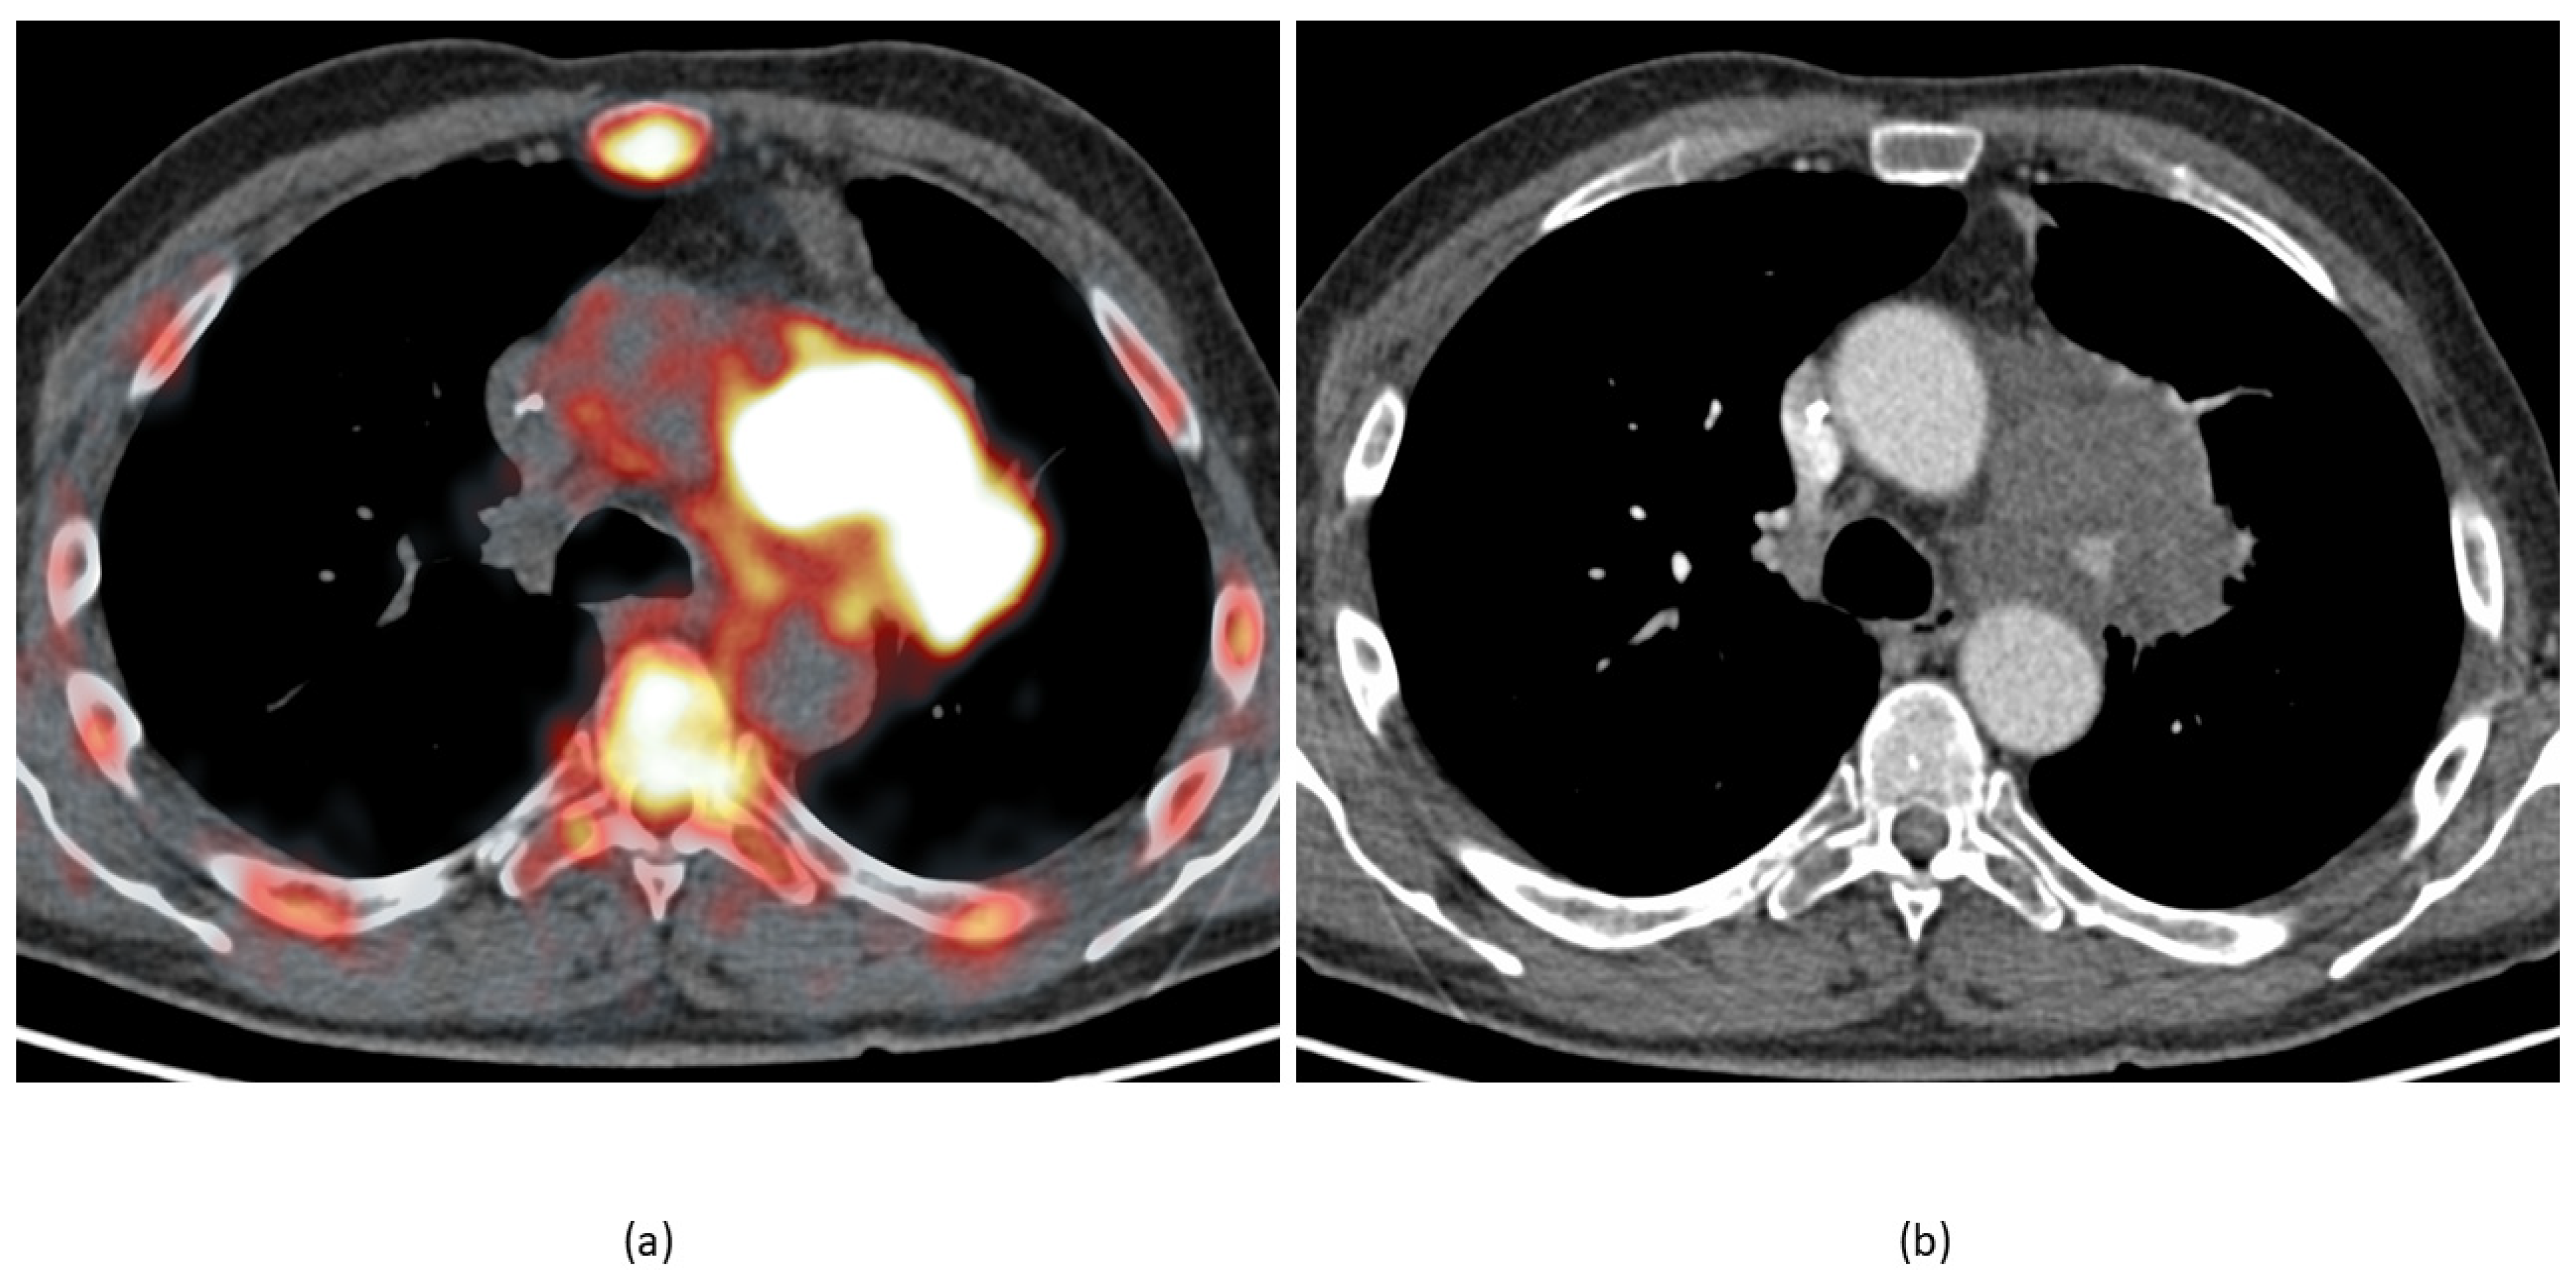

- Rominger, A.; Saam, T.; Vogl, E.; Übleis, C.; la Fougère, C.; Förster, S.; Haug, A.; Cumming, P.; Reiser, M.F.; Nikolaou, K.; et al. In Vivo Imaging of Macrophage Activity in the Coronary Arteries Using 68Ga-DOTATATE PET/CT: Correlation with Coronary Calcium Burden and Risk Factors. J. Nucl. Med. 2010, 51, 193–197. [Google Scholar] [CrossRef]

- Tarkin, J.; Joshi, F.R.; Evans, N.R.; Chowdhury, M.M.; Figg, N.L.; Shah, A.V.; Starks, L.T.; Martin-Garrido, A.; Manavaki, R.; Yu, E.; et al. Detection of Atherosclerotic Inflammation by 68Ga-DOTATATE PET Compared to [18F]FDG PET Imaging. J. Am. Coll. Cardiol. 2017, 69, 1774–1791. [Google Scholar] [CrossRef] [PubMed]